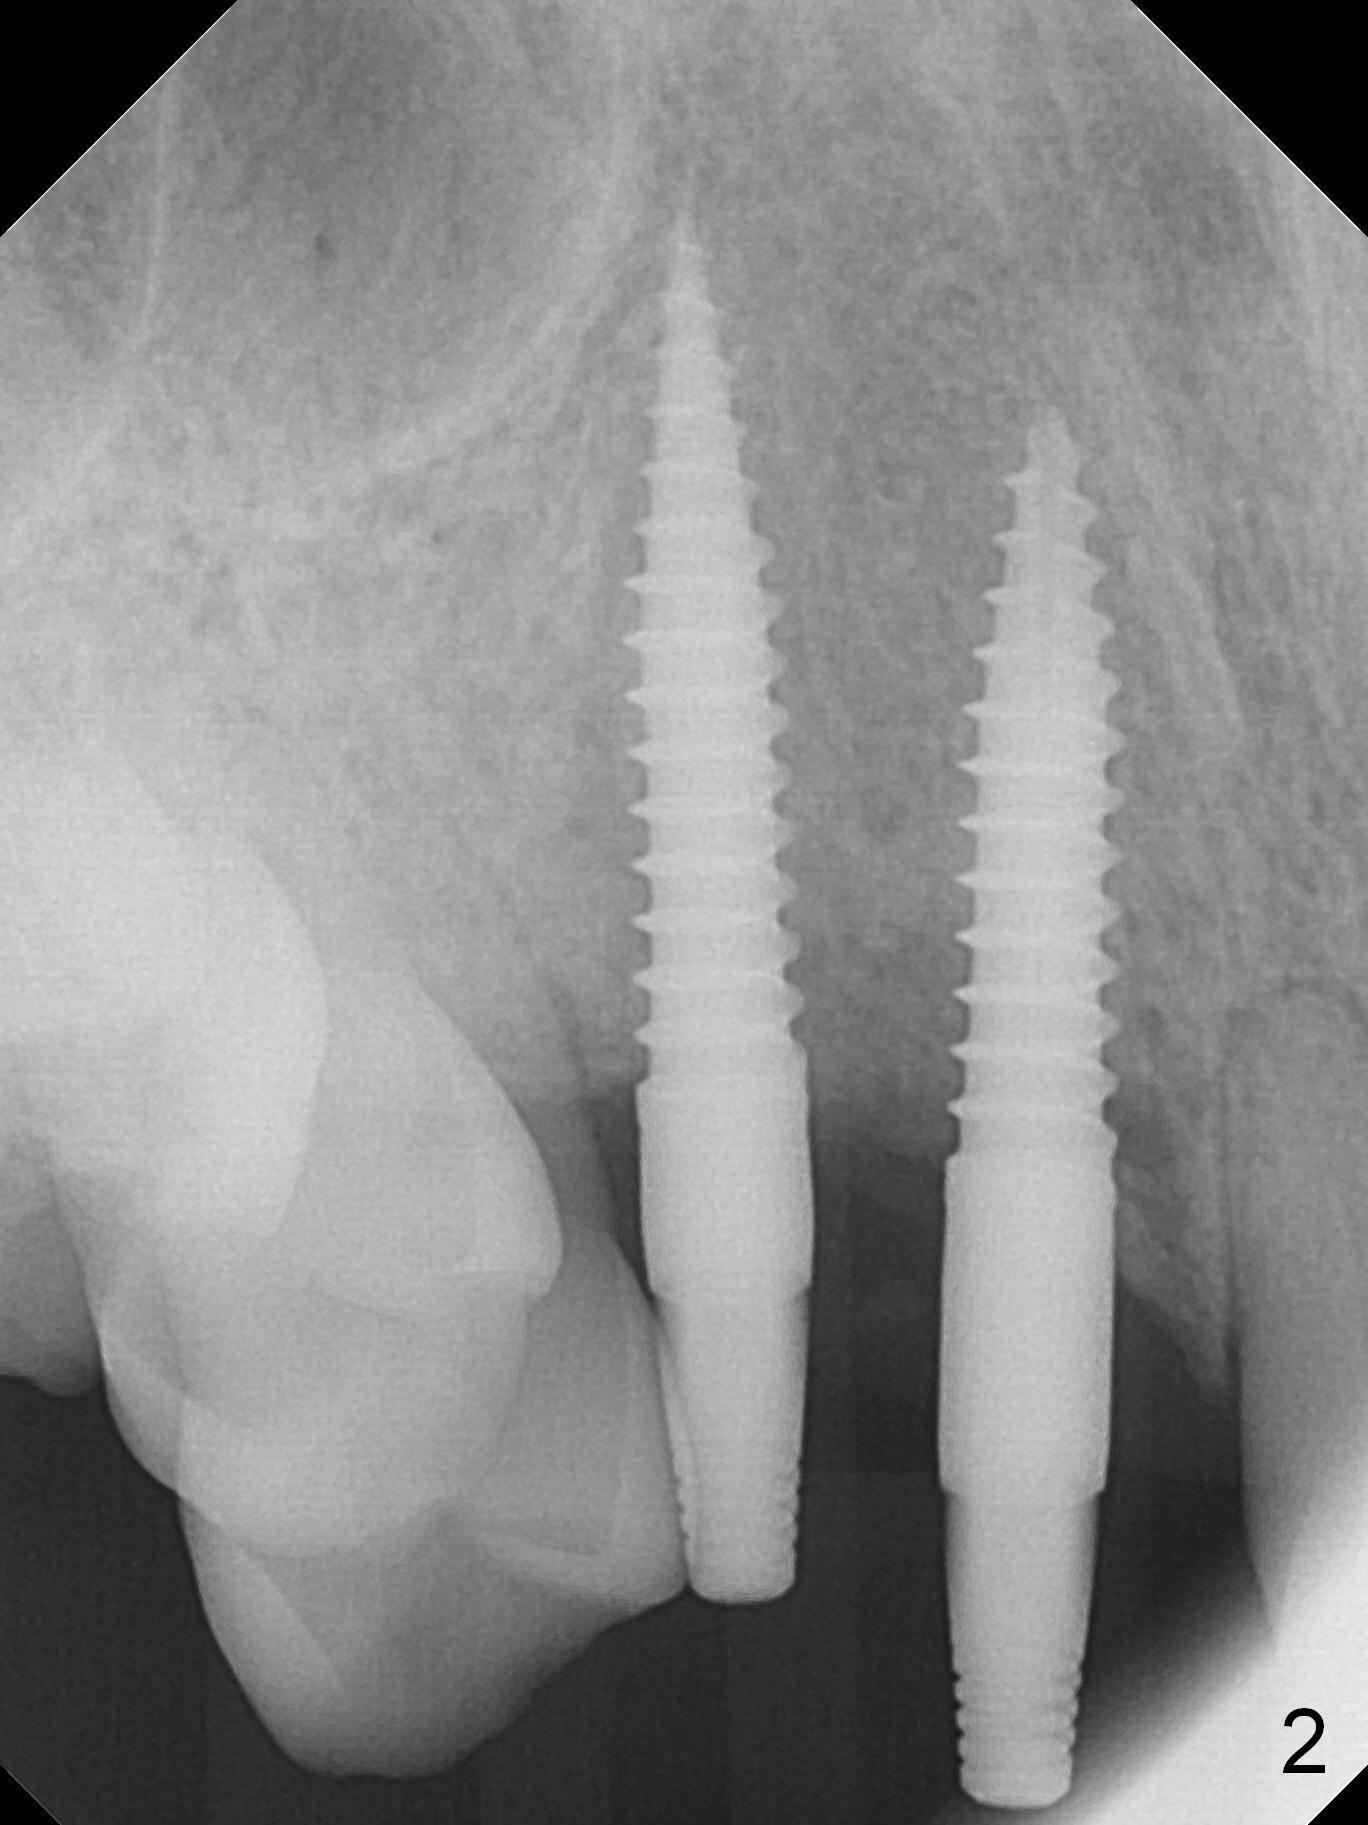

There is no bone loss 3 months postop (Fig.3). After reprep (Fig.4), shades are selected for the final crowns (Fig.5). Before crown cementation at #6 and 7, the patient notes asymmetry with the teeth on the other side (Fig.6). Our concerns are the lack of the papilla distal to #6 (Fig.7 * (multiple modification of provisional needed)) and slight inflammation due to insufficient oral hygiene (^).